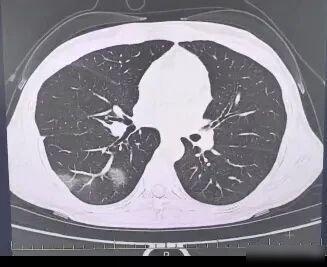

杭州女高管硬扛流感险丢命,福州女孩停药肺部实变,今冬流感为何突然凶猛? 35岁的杭州女高管,发烧了三天没当回事,体温一下子冲到39.7度,结果去医院一查,发现是白肺,血氧掉到88%,住了七天医院才缓过来,福州那边一个12岁小女孩,因为中间自己停了药,右肺出现大面积实变,这可不是单独一例,今年冬天流感正从学生往上班族和中老年人身上扩散,甲型H3N2是主要类型,全国阳性率差不多快到一半了。 医生说得很直接,流感不是普通感冒,在48小时之内吃下抗病毒药物能够救人一命,要是拖过了这个时间点,危险就会增加很多,现在药店里有国产的新药玛巴洛沙韦干混悬剂可以买到,但大家不要自己随便用,一定要听医生的话,疫苗就算现在打也还是有用,总比什么都不做要好。 你身边有人最近出现发烧咳嗽的情况吗,他们是不是想着扛过去就算了,这次可千万不能不当回事。 普通流感症状比新冠弱或者一样吗?